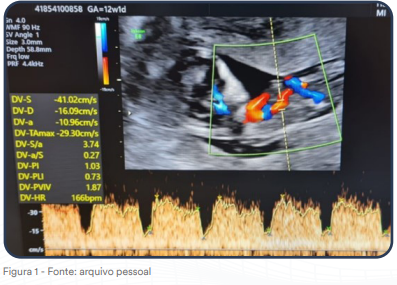

Gestante de 12 semanas e 1 dia realiza ultrassom morfológico de primeiro trimestre conforme a imagem a seguir.

Assinale a alternativa que corresponde adequadamente ao vaso sanguíneo analisado na figura 1 e a sua correspondente posição na circulação fetal na figura 2.